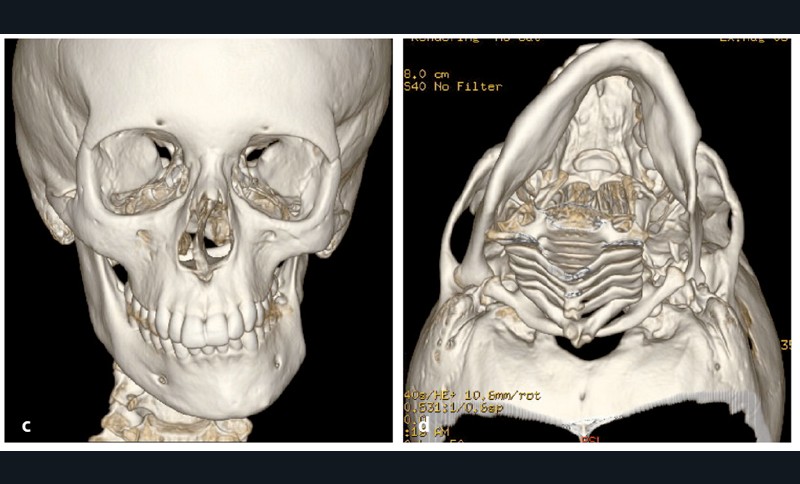

Analyse squelettique : les documents montrent une classe II squelettique modérée par rétrognathie mandibulaire dans un contexte de normodivergence. Les examens complémentaires confirment que la latérognathie mandibulaire gauche est la conséquence d’un hypo-développement des structures maxillaires et mandibulaires de ce même côté (fig. 2a, b et c). On observe sur les reconstructions 3D (à partir des coupes scanner) à l’aide du logiciel Osirix® : un corps mandibulaire fin, un ramus peu développé, un col du condyle grêle.